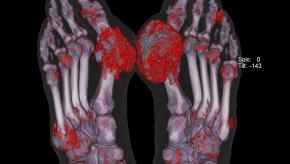

DECT Evidence of Urate Deposition is Associated with X-ray Damage in Gout

Dalbeth and coworkers studied 92 patients with gout and using DECT scanning have shown those with urate deposition on DECT were 8.5-fold more likely to have erosive disease on plain radiographs.